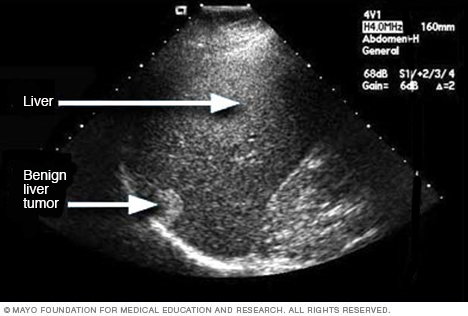

Ultrasound of liver tumor

An ultrasound uses sound waves to create an image. This ultrasound shows a noncancerous liver tumor.